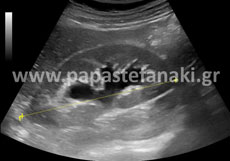

Υπερηχογράφημα Άνω Κοιλίας

Τα όργανα που ελέγχουμε είναι το ήπαρ, η χοληδόχος κύστη, το πάγκρεας, οι νεφροί, ο σπλήνας, ο οπισθοπεριτοναϊκός χώρος, το έντερο και τα τοιχώματα της κοιλίας.